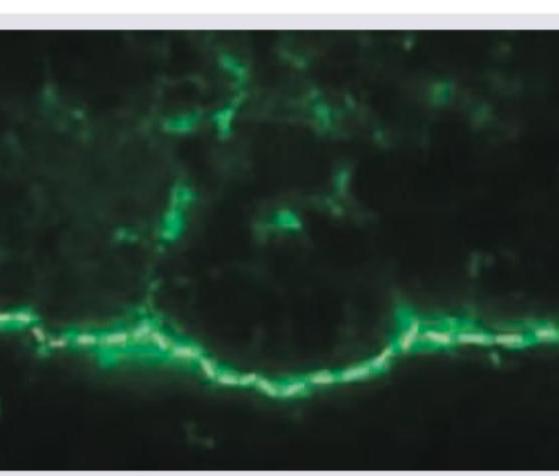

Explanation: ***Pemphigus vulgaris*** - The direct immunofluorescence image shows a characteristic **"chicken wire"** or **intercellular** staining pattern in the epidermis. - This pattern indicates the presence of autoantibodies (typically **IgG**) targeting **desmoglein 1 and 3** in the desmosomes, leading to intraepidermal blistering, which is a hallmark of pemphigus vulgaris. *Bullous pemphigoid* - Direct immunofluorescence in bullous pemphigoid typically shows a **linear deposition of IgG and C3 along the dermal-epidermal junction** (basement membrane zone). - This pattern is distinctly different from the intercellular epidermal staining seen in the image. *Cicatricial pemphigoid* - This condition also presents with **linear deposition of immunoreactants along the basement membrane zone**, similar to bullous pemphigoid, but with a different antigen target. - The image does not show a linear basement membrane pattern, ruling out cicatricial pemphigoid. *Chronic bullous dermatosis of childhood* - Also known as **linear IgA bullous dermatosis**, it is characterized by a **linear deposition of IgA along the basement membrane zone**. - The image clearly displays an intercellular staining pattern within the epidermis, not a linear pattern at the dermal-epidermal junction.

Explanation: ***Pemphigus vulgaris*** - The combination of **flaccid blisters/erosions** on the skin and **buccal mucosal lesions** is characteristic of pemphigus vulgaris. The image showing **intercellular IgG deposits** (a "chicken wire" pattern) in the epidermis confirms the diagnosis on immunofluorescence. - Pemphigus vulgaris is an **autoimmune blistering disease** caused by autoantibodies against **desmoglein 1 and 3**, leading to acantholysis (loss of cell adhesion) within the epidermis. *Bullous pemphigoid* - This condition typically presents with **tense bullae** that are less prone to rupture, and **mucosal involvement is rare**. - Immunofluorescence in bullous pemphigoid shows **linear IgG and C3 deposits at the dermoepidermal junction**, not an intercellular epidermal pattern. *Linear IgA disease* - Characterized by **linear IgA deposition along the basement membrane zone** on direct immunofluorescence. - Clinically, it presents with **blisters** that can be variable in appearance, but the pathognomonic immunofluorescence pattern is distinct. *Dermatitis herpetiformis* - Presents with very **pruritic vesicles and papules**, primarily on extensor surfaces, and is strongly associated with **celiac disease**. - Direct immunofluorescence reveals **granular IgA deposits in the dermal papillae**, which is distinct from the intercellular IgG pattern seen here.